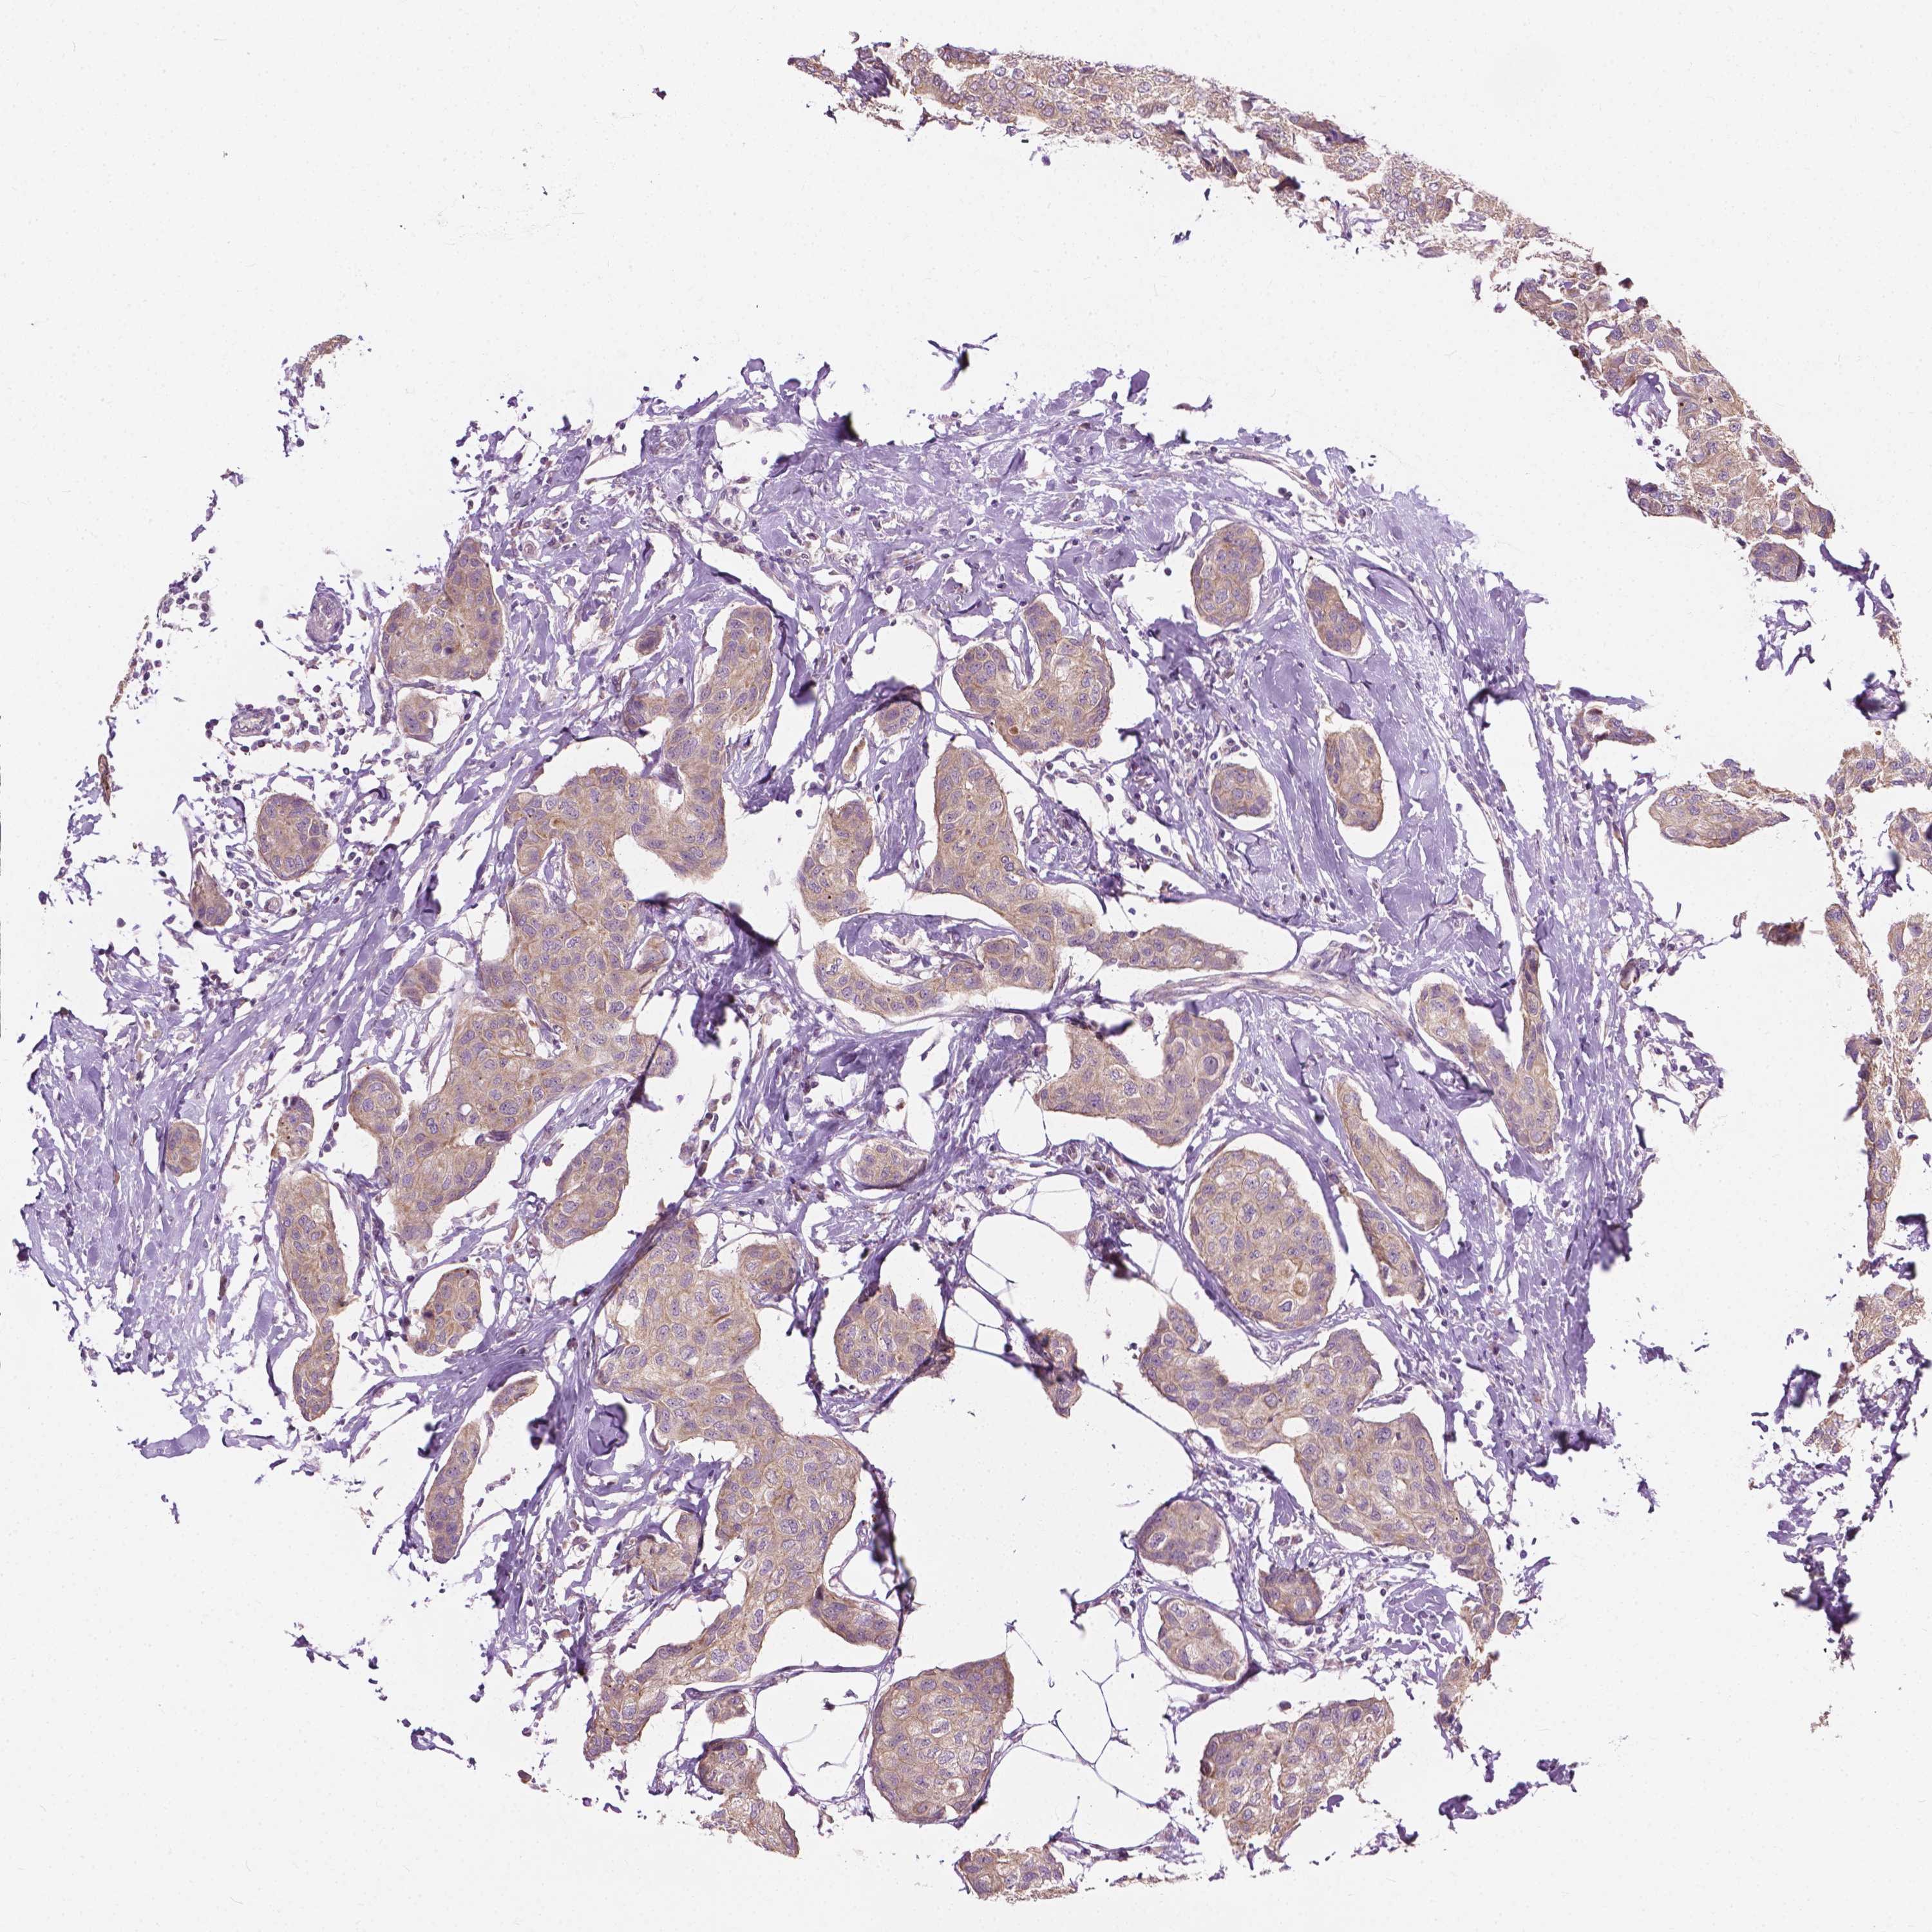

CANCER BREAST CANCER Show tissue menu

BRCA TCGA BRCA VALIDATION PROTEIN EXPRESSION